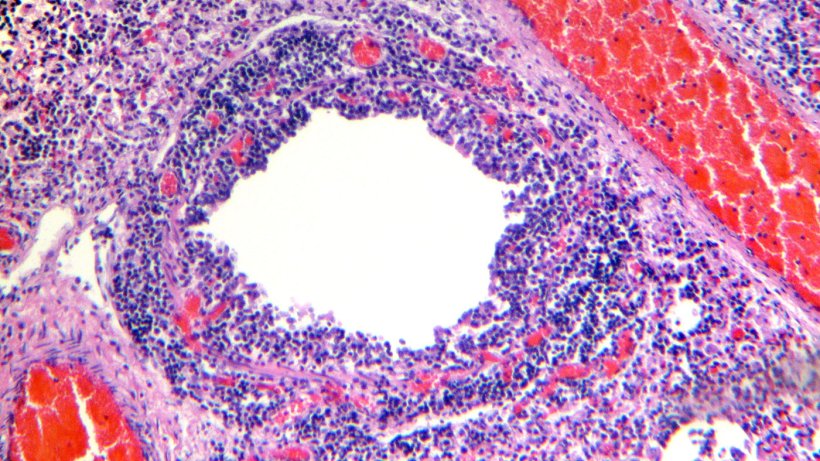

Badanie histologiczne tkanki płuc wykazało naciek limfocytarny na blaszkę właściwą i podśluzówkę oskrzeli. (Ryc. 4 i 5).

Ryc. 5. Okołonaczyniowy naciek limfocytarny.

Ryc. 4. Oskrzelik - widoczne rozwarstwienie i martwica nabłonka oddechowego, wzdłuż którego widoczny jest naciek limfocytarny na blaszkę właściwą i podśluzówkę.